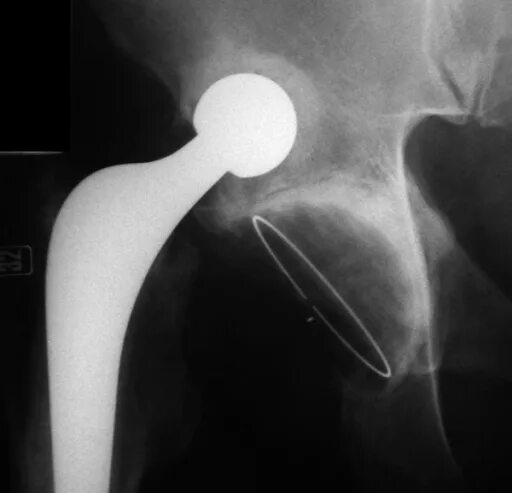

Расшатывание эндопротеза тазобедренного сустава